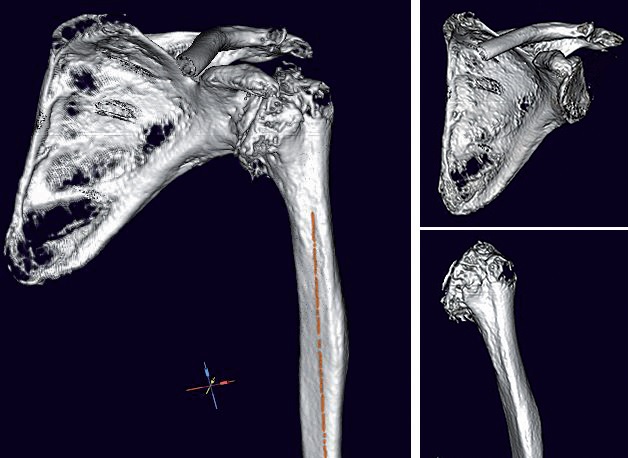

Ich versuche bei jeder anstehenden OP mindestens eine digitale 2D-Planung, idealer Weise sogar eine 3D-Planung zu

machen. 3D-Planungen basieren aber auf CT-Bildern, und leider habe ich nicht immer ein geeignetes CT in der entsprechenden

Dünnschicht-Auflösung und Abmessung (ganzes Schulterblatt und Epicondylen ) zur Verfügung, denn viele Patienten

haben nur ein MRT dabei, bei dem meist nicht die eigentlich erforderlichen Endpunkte der betroffenen Knochen

abbgebildet sind und gehen davon aus, dass dies ausreichend sei. Eine digitale 2D-Planung ist aber auch anhand eines

MRT in Annäherung möglich, allerdings mit deutlich eingeschränkter Aussage gegenüber der 3D Planung mit reproduzierbaren

Referenzebenen in den Schulterblattebenen und Humerusachsen.

Deswegen bin ich gerade dabei mit unseren ortsansässigen Radiologen ein mediCAD® CT-Protokoll zu erarbeiten und

dabei die Vorteile der 3D-Planung mit Bestimmen auch der Humerus-Retrotorsion durch Erfassen der Epicondylenachse

zu erklären. Problem dabei ist allerdings, wie so oft, die Vergütung. Das erforderliche CT ist für den Radiologen mit

Weiterer Vorteil von von mediCAD® Shoulder 3D ist, dass der Operateur mit der Software selbst (und nicht irgendein

Ingenieur des Implantatherstellers) die Segmentierung des CT-Datensatzes durchführen kann, entsprechend seiner medizinischen

Erfahrung und Interpretation der CT Bilder. Außerdem sind das Erstellen eines 3D-Modells und die Möglichkeit

der anschließende Planung von Glenoid und Humerus einzeln hintereinander möglich. Auch die vollständige

Gelenkplanung nach der Reposition des Gelenkes mit implantierten Komponenten sind Funktionen, die ich als Arzt nicht

missen möchte. Und natürlich die 3D-ROM-Analyse des reponierten Gelenkes bei innenliegender Prothese.